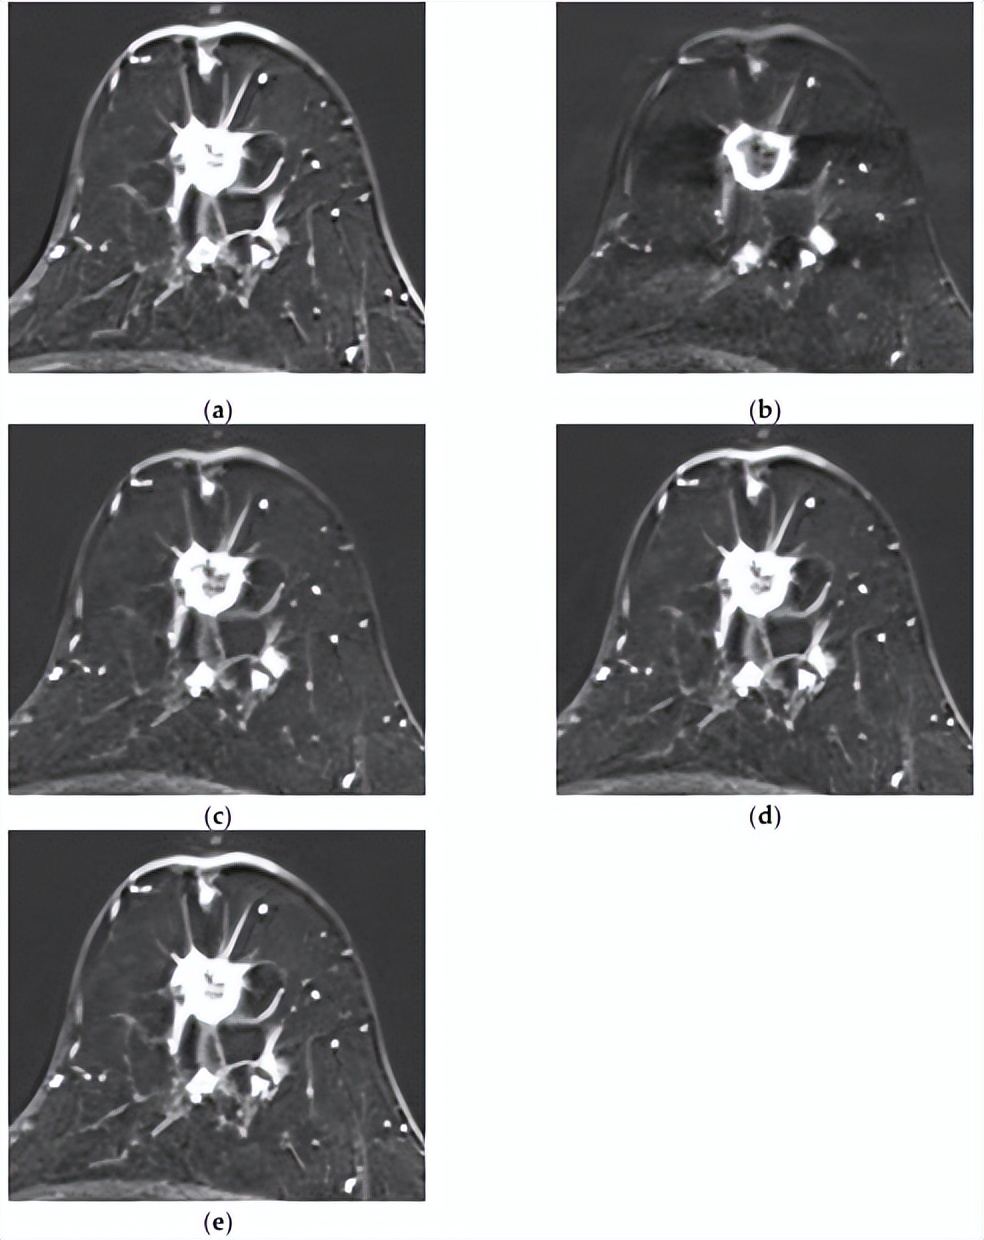

[组合模型正确预测了复发,而MRI模型则没有。一名73岁的女性,乳房几乎完全脂肪化,BPE极小。注射造影剂后(a)1分钟、(b)2分钟、(c)3分钟、(d)4分钟和(e)5分钟的轴向增强T1加权MR图像显示,右下内象限有一个1.4×1.7厘米的不规则形状、边缘不规则肿块,内部增强不均匀。病灶表现出快速的初始增强,随后呈现平台期动力学曲线模式。未发现腋窝淋巴结转移。MRI深度学习模型无法预测该复发病例,但整合临床病理学和MRI特征的组合模型可以正确预测。]